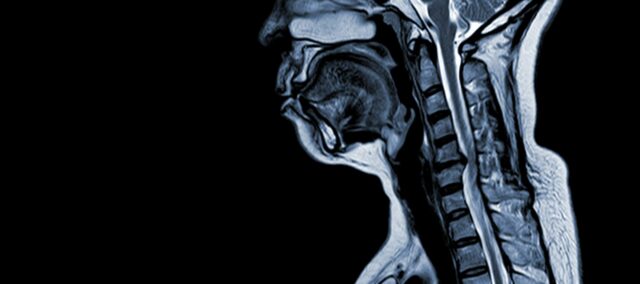

La mielopatía cervical espondilótica (MCE) es una afección neurológica que constituye la principal causa de lesión medular en adultos. En términos sencillos, consiste en la compresión o daño de la médula espinal en el cuello, principalmente debido al proceso natural de envejecimiento que afecta a las vértebras cervicales. El término "mielopatía" procede de las palabras griegas "myelon", que significa "médula espinal", y "pathos", que significa "enfermedad".

La MCE es una afección médica compleja con una fisiopatología multifactorial que incluye cambios estructurales en la columna cervical. Varios factores clave contribuyen a su desarrollo y progresión:

- Degeneración discal (disco abultado): La MCE suele comenzar con la degeneración de los discos intervertebrales de la columna cervical, lo que provoca su abombamiento o protrusión en el canal espinal.

- Formación ósea subperióstica (ventral al canal medular): En respuesta al aumento de la tensión mecánica, el cuerpo forma nuevo tejido óseo en la parte frontal (ventral) del canal espinal, lo que puede estrechar el espacio para la médula espinal.

- Osificación del ligamento longitudinal posterior: El ligamento longitudinal posterior puede osificarse, endurecerse y calcificarse, contribuyendo al estrechamiento del canal espinal.

- Hipertrofia del Ligamentum Flavum: La hipertrofia del Ligamentum Flavum hace que se vuelva más grueso y menos flexible, invadiendo aún más el espacio dentro del canal espinal y comprimiendo la médula espinal.

Estos cambios estructurales conducen colectivamente a la compresión y el estrechamiento del canal espinal, lo que provoca los síntomas característicos y las complicaciones asociadas a la MCE. Reconocer estos factores de riesgo y comprender los mecanismos fisiopatológicos implicados es esencial tanto para la prevención como para el tratamiento. El diagnóstico precoz y las intervenciones adecuadas son cruciales para mitigar los efectos de estas alteraciones estructurales en la médula espinal.